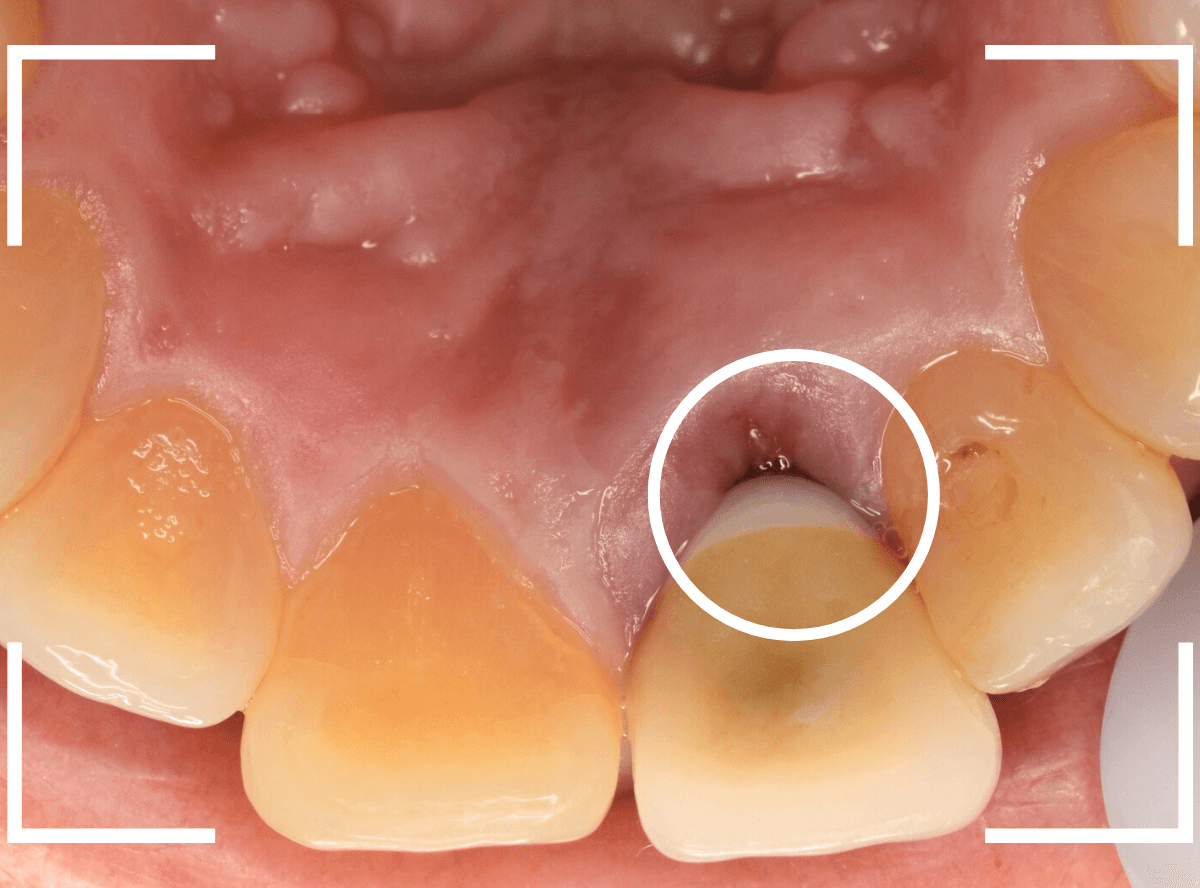

今回は、上の前歯を抜歯した後に放置してしまったので、そろそろ綺麗に作り直したいという患者さんです。

インプラント治療もご提案したのですが、セラミックのブリッジ治療をご希望されました。

ブリッジ治療をする隣の歯も神経処置をした後の虫歯になっていますので、4本同時に治療する事になりました。

まずは虫歯のある歯の治療とファイバーコアのsetを行い、支えとなる歯(支台歯)の形を整えます。

完成の前に、ジルコニアフレームにワックスを盛ったもので、患者さんと完成型のシュミレーションをします。

患者さんからも、ゴーサインをもらったのを確認して、完成させます。

微調整をして、最終setしたところです。

患者さんにも満足していただけたようで、ホッとしました。

セラミックの舌触りにも驚かれていました。

治療前後の比較です。

治療はさし歯を入れて終わりではありません、末永く使うために、定期メンテナンスにも忘れずに来ていただくよう、お話しました。